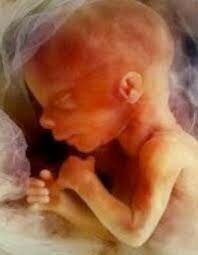

• Semana 12

Semana 12

Casi todos los órganos terminan de formarse, las excepciones son el encéfalo y la médula espinal que siguen formándose y madurando durante todo el embarazo

• Semana 13

Semana 13

El feto ya puede oír

• Semana 14

Semana 14

Puede identificarse el sexo del feto

• Semana 15

Semana 15

Los dedos del feto pueden agarrar. Los movimientos del feto son más vigorosos y la madre puede percibirlos.